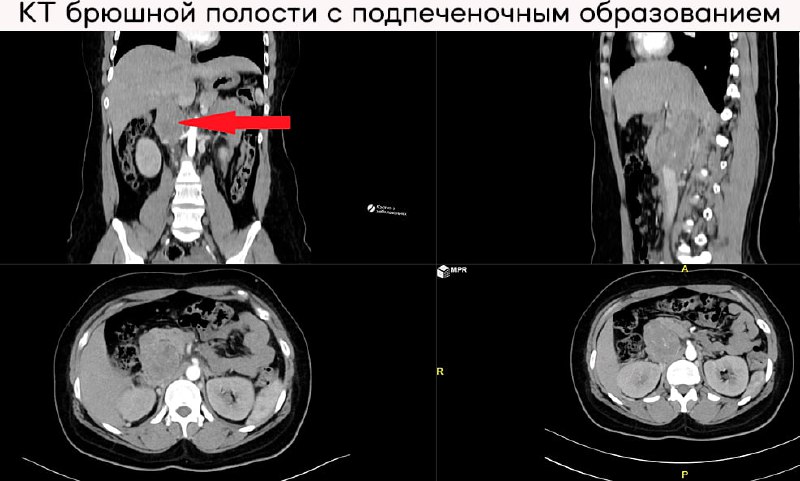

Клинический взгляд на резекцию лейомиосаркомы нижней полой вены - редкая опухоль гладких мышц:

1 мар. 2026 г.

1.5k 6 1